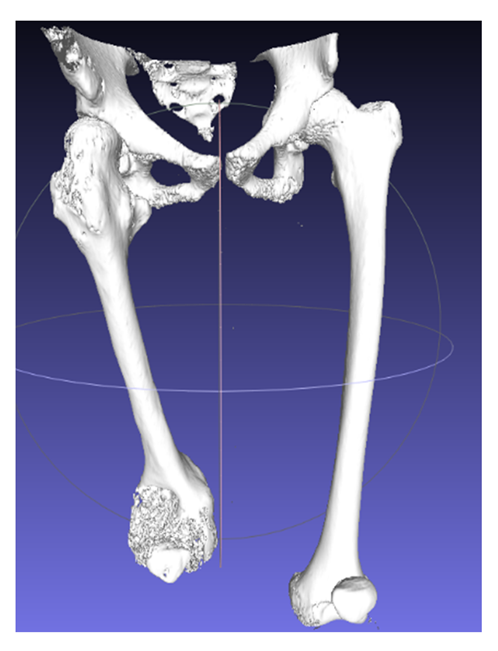

Seven different cases are reported in this study to verify the effectiveness of the CASS methodology and to identify any criticalities deriving from the great cases of pathology in the orthopedic field (Table 2). For all patients, the processing starts from a computerized tomography examination to obtain an optimized 3D model of the examined anatomy and, finally, the simulation of the surgery on CREO.

The first step concerns the conversion of tomographic images into a three-dimensional model. As mentioned, the images deduced from the CT are not always appropriately clear to allow the medical specialist to develop in detail the procedure to be performed before the operation, so the process is divided into three main phases in order to emphasize the exact region and create the 3D model, removing unnecessary anatomical parts. Computed tomography is converted to standard triangulation language (STL) to represent the examined anatomy in three dimensions, but the model is too heavy, computationally speaking, and is marked by a dense structure that must be optimized. To do that, MeshLab is used for the elimination of the inner material of no interest and the overlapped geometries, and MeshMixer for external surface and file format correction. The steps of this first part of the workflow are summarized below (in order: Figure 1 is the importation in InVesalius of the CT exam, Figure 2 is the processing to optimize the 3D surface obtained and Figure 3 is the correction of mesh errors.

The CASS process was achieved agreeing to the surgeons’ likings and experiences; thus, patients were not consecutive and the study was not randomized. Parents and carers provided authorization for the study. The methodology described and illustrated by the example of a Monteggia lesion has been applied to all the cases reported in Table 4. This resulted in seven different assembly files on CREO, each one representing the phases of the respective surgery. Applying simulation to more than one pathology, involving different body segments, has enabled its effectiveness to be verified and the problems to be solved or improved. Some of the cases have already been operated and the surgeons of Rizzoli were very satisfied with the results obtained in the pre-operative planning phase, finding a considerable reduction in risks and timing during the operating phase.